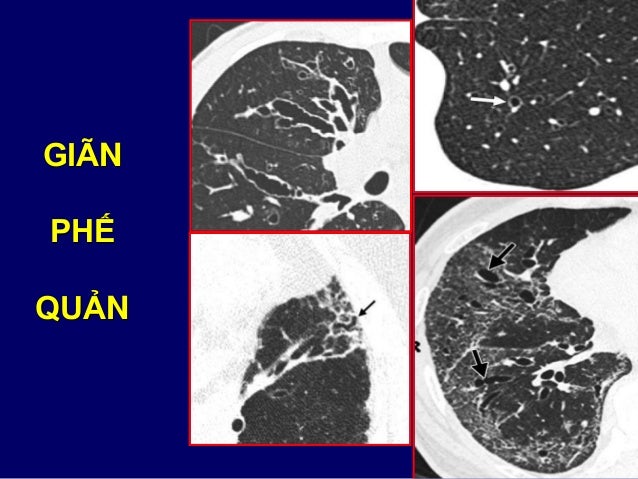

22. 22. Artère pulmonaire GArtère pulmonaire Dte

23. 23. CÁC THÙY & PHÂN THÙY PHỔI

45. 45. GIÃN PHẾ QUẢN

46. 46. GIÃN PHẾ QUẢN THÙY DƯỚI PHẢI